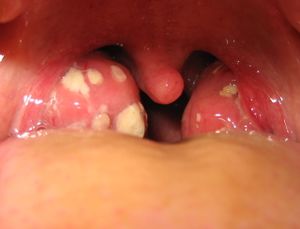

Enlarged, red tonsils and exudative white patches of tonsillitis | |

- احمرار اللوزتين مع وجود بقع بيضاء قيحية عليهما.

(التشخيص) يتم التشخيص بسهولة بفحص الفم مع استخدام خافض اللسان حيث تشاهد اللوزتان المتضخمتان مع وجود احمرار فيهما وبقع بيضاء قيحية أحياناً وقد نجد احمراراً في البلعوم أيضاً أما تأكيد سبب الالتهاب فيحتاج لإجراء مسحة البلعوم (أي اخذ عينة في البلعوم أو اللوزتين وزرعها.